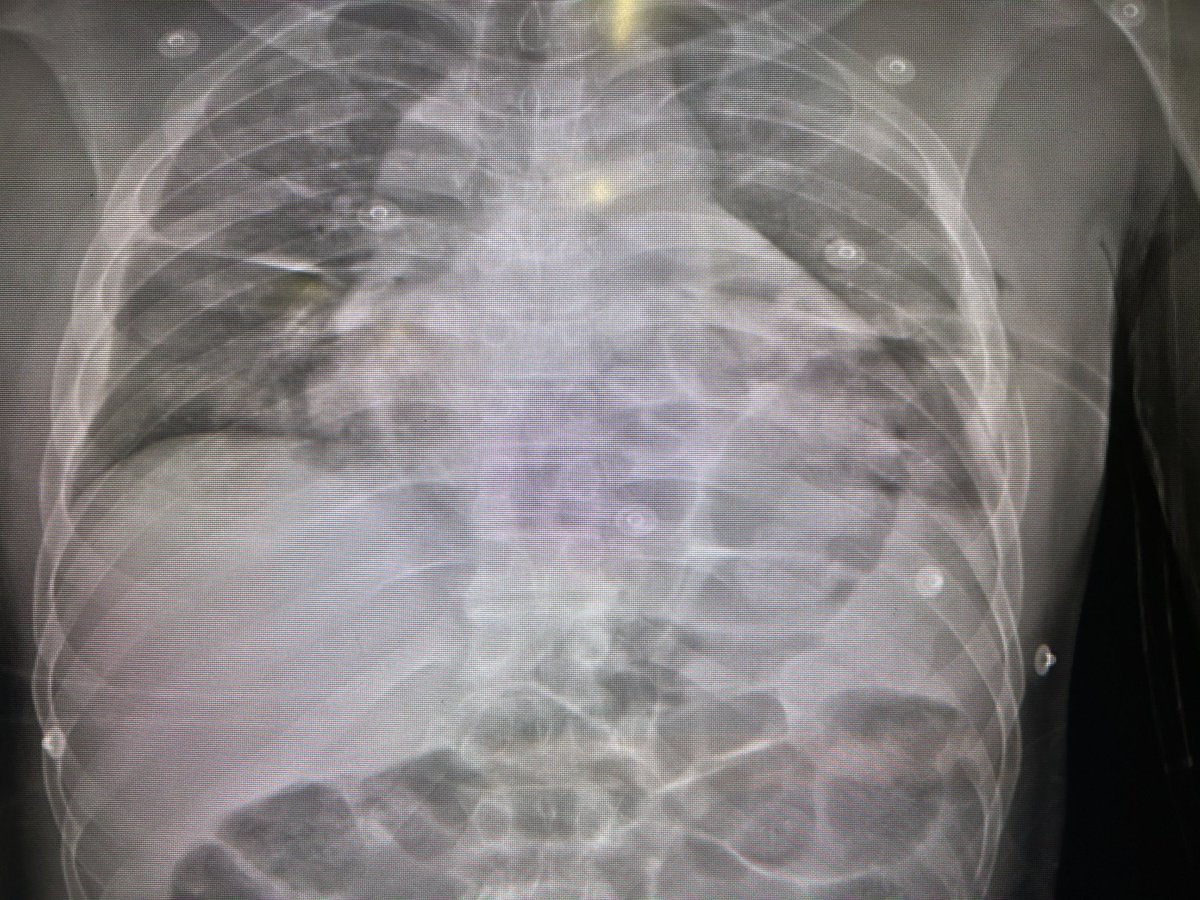

Post-Morten CT scan after fatal blunt trauma. Interesting findings from Jeremy H Levin at #EAST2023. Takeaway messages: Always decompress the chest. Always confirm the airway.

Post-Morten CT scan after fatal blunt trauma. Interesting findings from <a href="/JeremyHLevin/">Jeremy H Levin</a> at #EAST2023.

Takeaway messages:

Always decompress the chest.

Always confirm the airway.